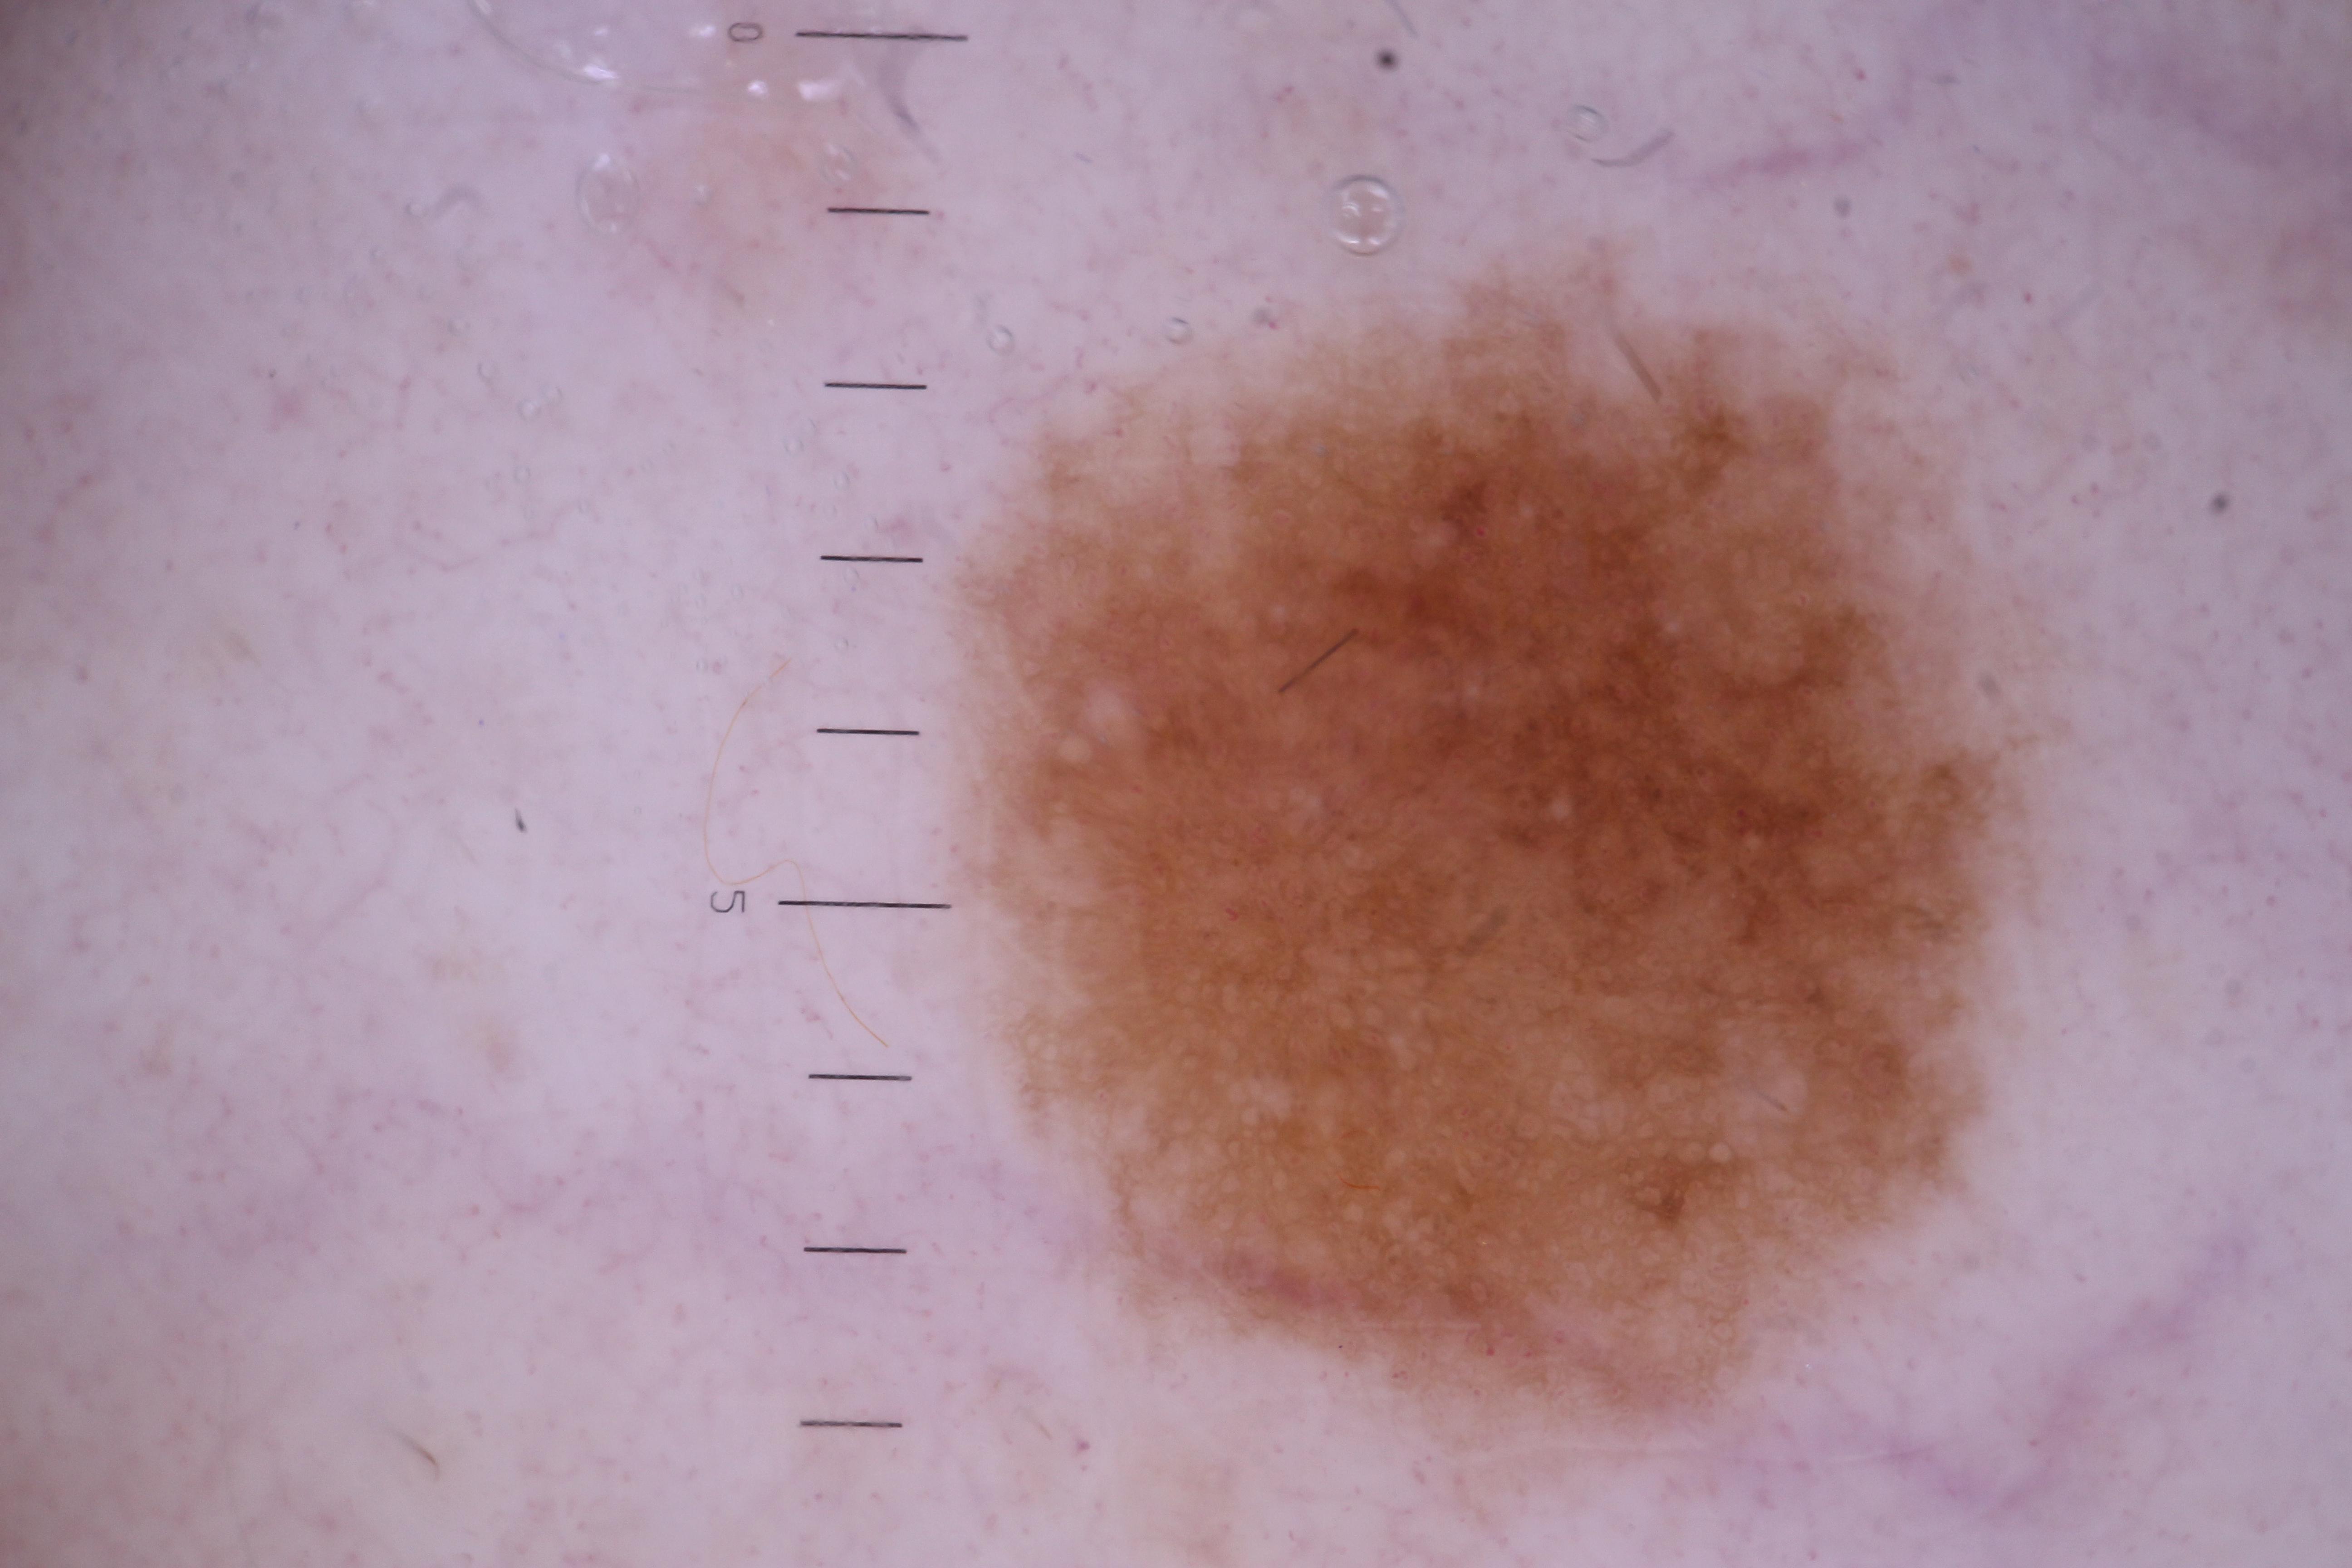

{

"acquisition_day": 3042,

"age_approx": 80,

"anatom_site_general": "upper extremity",

"concomitant_biopsy": false,

"diagnosis_1": "Benign",

"diagnosis_confirm_type": "serial imaging showing no change",

"fitzpatrick_skin_type": "II",

"image_type": "dermoscopic",

"lesion_id": "IL_1084919",

"patient_id": "IP_1665515",

"sex": "male"

}